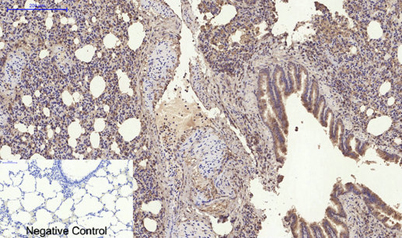

Product name: RANKL rabbit pAb

Dilutions: Western Blot: 1/500 - 1/2000. IHC-p: 1:100-300 ELISA: 1/20000. IF 1:100-300 Not yet tested in other applications.

Immunogen: The antiserum was produced against synthesized peptide derived from the C-terminal region of human TNFSF11. AA range:268-317